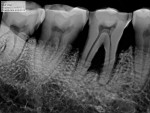

With respect to diagnostic image quality, the Z-image software displays high-resolution images from the Z-ray sensor with great contrast because the images have less noise. Additionally, the 16-bit capture provides the broadest grayscale range to reveal fine details even when zoomed in on a specific region. The Z-image software has state-of-the-art filters that enhance the image with various adjustments like sharpness, contrast, brightness, gamma, and curve adjustments. This lets me see the specifics of a certain anatomic region. There are filters that can be applied in a single click for endodontics, periodontics, general dentistry, and restorative. These filters help me see exactly what I need to see in clinically relevant ways without having to tinker with the manual filters individually.